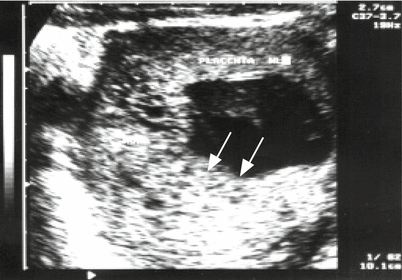

Summary Obgyn Multiple Gestation Royal College Of Surgeons Ireland A multiple gestation is considered a maternal health condition — a condition in the mother that may affect the baby or pregnancy. as exciting and joyful as a multiple birth is, it also increases the risk of such conditions as gestational diabetes, anemia, preeclampsia, and miscarriage. Screening, surveillance, and management strategies are delineated succinctly and organized by type of multiple gestation being managed from the lowest risk dichorionic twin pair to the increasingly escalating risks of twins and higher order multiples sharing a placenta and or amniotic sac. A comprehensive guide to understanding multiple pregnancies (twins, triplets, etc.), detailing the associated risks for mother and babies, methods of diagnosis, and crucial management strategies to ensure the healthiest possible outcomes. Find best ob gyns in los angeles, california & make an appointment online instantly! zocdoc helps you find ob gyns in los angeles and other locations with verified patient reviews and appointment availability that accept your insurance.

Multiple Gestation Obgyn Key At advanced perinatology, we provide expert maternal fetal care for all pregnancies, ensuring the best possible outcomes for both mother and baby. our team of board certified perinatologists offers cutting edge diagnostics, compassionate support, and personalized treatment plans. "the best ob gyn i've had to date! and i have a lot. she's got a terrific, outstanding bedside " more. At the fetal maternal center at children’s hospital los angeles, we provide care for complex fetal conditions. when routine tests show the possibility of a medical problem, pregnant women come to our program for diagnosis and treatment. Multifetal gestations have increased risks to the pregnant patient and the fetus and neonate, including gestational diabetes, preeclampsia, preterm delivery, growth restriction, postpartum hemorrhage, and stillbirth or neonatal death.

High Risk Pregnancy Ob Gyn In Nyc Maiden Lane Medical At the fetal maternal center at children’s hospital los angeles, we provide care for complex fetal conditions. when routine tests show the possibility of a medical problem, pregnant women come to our program for diagnosis and treatment. Multifetal gestations have increased risks to the pregnant patient and the fetus and neonate, including gestational diabetes, preeclampsia, preterm delivery, growth restriction, postpartum hemorrhage, and stillbirth or neonatal death.